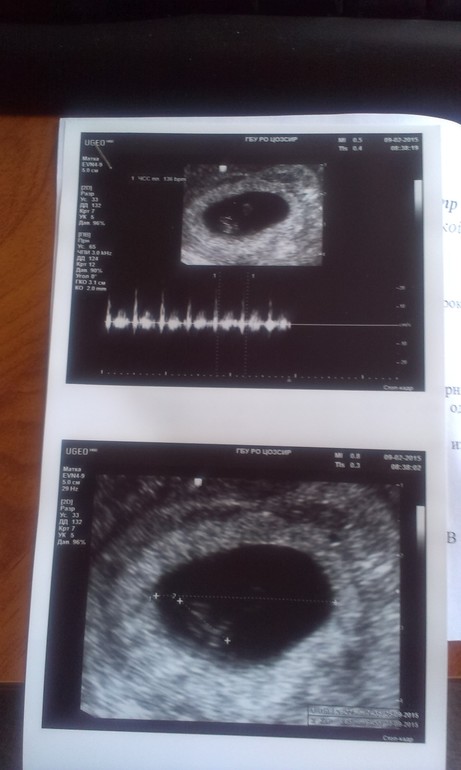

Результаты: УЗИ, КТГ, доплера, скринингаИтак,потеряв на несколько дней чувство беременности,я решила сходить на узи.

Плодное яйцо 26 мм

Ктр 9 мм

Сердцебиение 136 ударов в минуту

Хорион по задней стенке

Желточный мешок 5 мм Подросло всё,кроме желточного мешочка и меня это немного беспокоит.Кстати,на первом узи хорион был по передней стенке,он что,переместился?И как думаете,девочки,остальные показатели в норме?

ну и наши первые фото))))